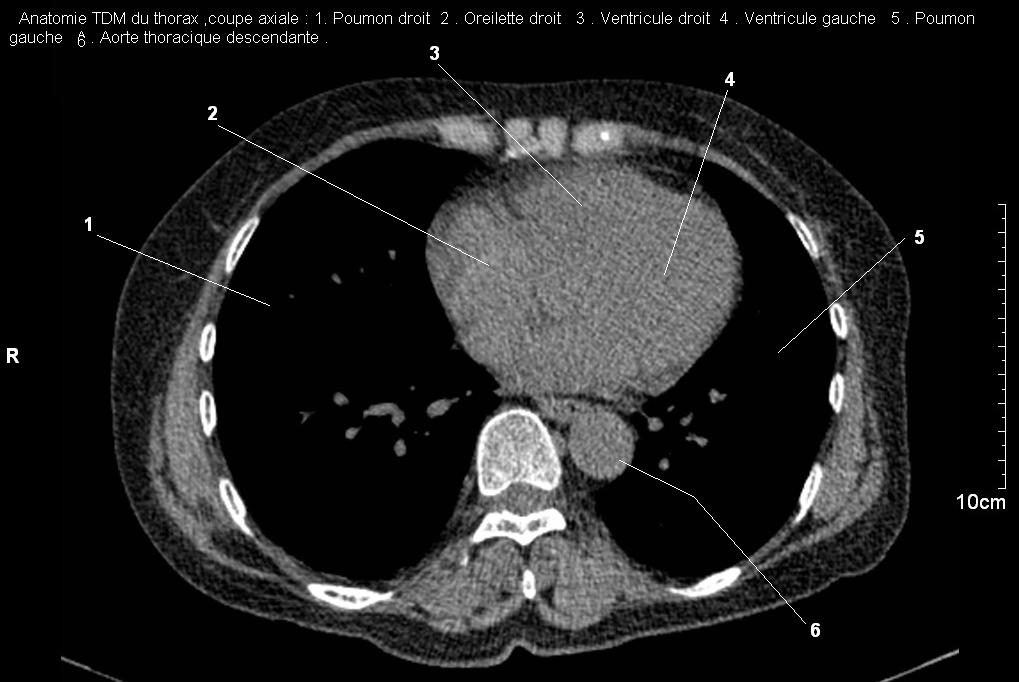

Radioanatomie pulmonaire ( image radiologie

thoracique normale )- La Tomodensitometrie du thorax (

coupes axiales fenetre mediastinale ) |

La fenetres mediastinale permettre

d'etudier anatomie du mediastin et les structures vasculaires

en coupes axiales de 0,5-1cm sur le thorax . Ceux qui

s'installent travers le thorax de C4 a L1, L2

a n'a pas de contrast et se donnent des resutats

suivantes : |